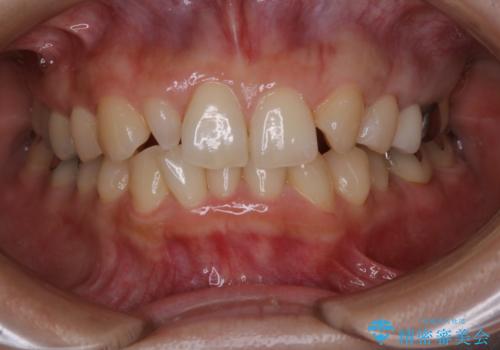

- 冷たいものを飲むと右下の奥歯が痛むので診て欲しいといらっしゃった方の症例です。

銀歯及び虫歯を除去後、より適合の良いPGA(ゴールド)インレーによる修復を行いました。